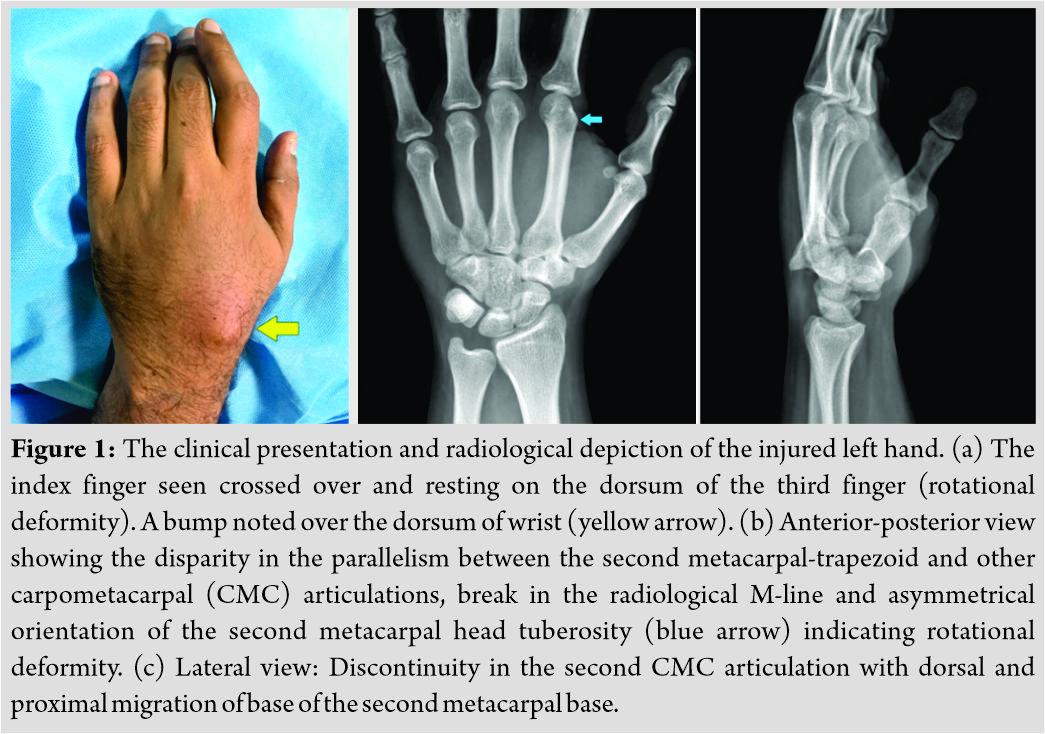

A 32-year male information technology employee experienced a road traffic accident and sustained direct impact injury to the left hand. He presented to the emergency department with pain, localized swelling over dorsum of the left hand, rotational deformity of index finger, and inability to form a complete fist. There were no associated injuries, and the patient was hemodynamically stable. On examination of the left hand (Fig. 1a), the index finger was appeared rotated and crossed over the dorsum of the middle finger. There was tenderness at the base of the second metacarpal and localized bony prominence over the wrist.The index finger appeared to have hyperextension at the metacarpophalangeal (MCP) joint, and flexion at the interphalangeal (IP) joints with the inability to flex or extend when attempted to form a fist giving the appearance of a pointing index finger (Video 1). Plain radiographs of the left hand revealed a dislocation of metacarpal-trapezoidal joint with dorsal and proximal migration of the second metacarpal (Fig. 1b and c).